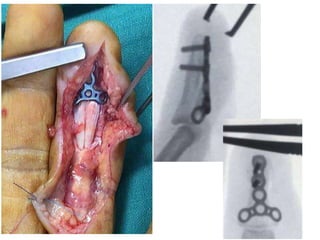

Zone 1

• Leddy type I – treat within 3 weeks

• type II and III treatable even after 6 weeks.

• Ultrasound helpful in locating the proximal

stump.

• Microsuture anchors or ORIF if bone fragment

• Ensure tendon-bone contact before final knot-

tying.

• Too tight repair - quadrigia.

• > Two-strand repair techniques

Leddy Packer Type III